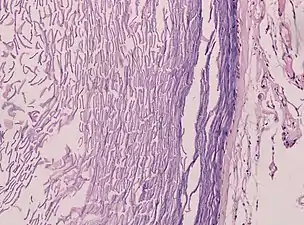

Epidermoid cysts are usually diagnosed when a person notices a bump on their skin and seeks medical attention. The definitive diagnosis is made after excision by a pathologist based on microscopic appearance of a cystic lesion lined by cornified epithelium containing lamellated keratin without calcifications. They can also be seen as isointense lesions on MRI or hyperintensities on FLAIR.

Histopathology, showing a keratinizing stratified squamous epithelium, and a lumen containing keratin flakes

Histopathology showing epithelium and lamellated keratin (left)